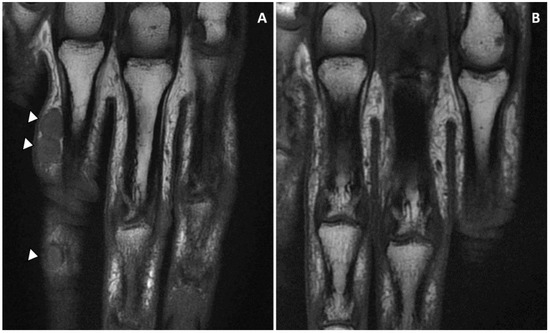

Magnetic resonance imaging (MRI) showed a subcutaneous thick-walled nodular structure at the second phalanx and a second bi-lobed nodule at the proximal phalanx of the fourth finger with no extension beyond the hypodermis, and no tendon or bone involvement (Figure 4).

Figure 4. (A) The nodules on the first (bi-lobed) and the second phalanx of the fourth finger (right hand) were revealed by MRI imaging. The lesions were limited to the subcutaneous tissue with no tendon and bone involvement. (B) MRI imaging confirmed the complete remission at six months follow-up.